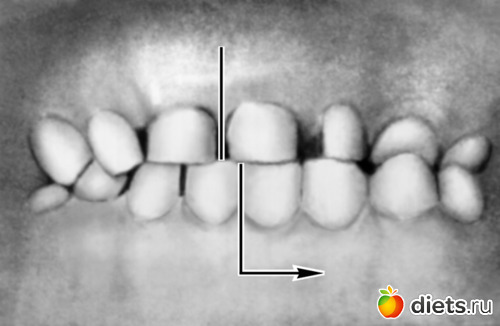

Так что я написать то решила. Мы поехали к ней, врачу. Вот я сказала что пластики на ночь не ношу, т.е. месяц не по носила и они стали не как раз. Вот она сказала что у меня есть зародыши зубов мудрости ( у меня какое-то запоздало развитие просто наверное...) Вот наверху под них вообще места нет. Т.е. наверху 100% вырывать их надо т.к. будут они рости просто в щеку. А внизу их вообще нужно убрать прям сейчас, ну как можно раньше т.к. челесть узкая и вот зубы еще больше внизу поедут... Предложила либо развигать эту дырку наверху (которую 3.5 года сдвигали) и вставлять туда импоанты, но это сразу не вариант, мама да и врач сказала, что не очень это удобно да и хорошо. 2 вариант удалять 4 зуб внизу и сдвигать зубы брекитыми, опять, т.к. сейчас у перекрестный прикус (фото).

(на фото только выпирает челюсть)

(на фото только выпирает челюсть)

(на фото только выпирает челюсть)